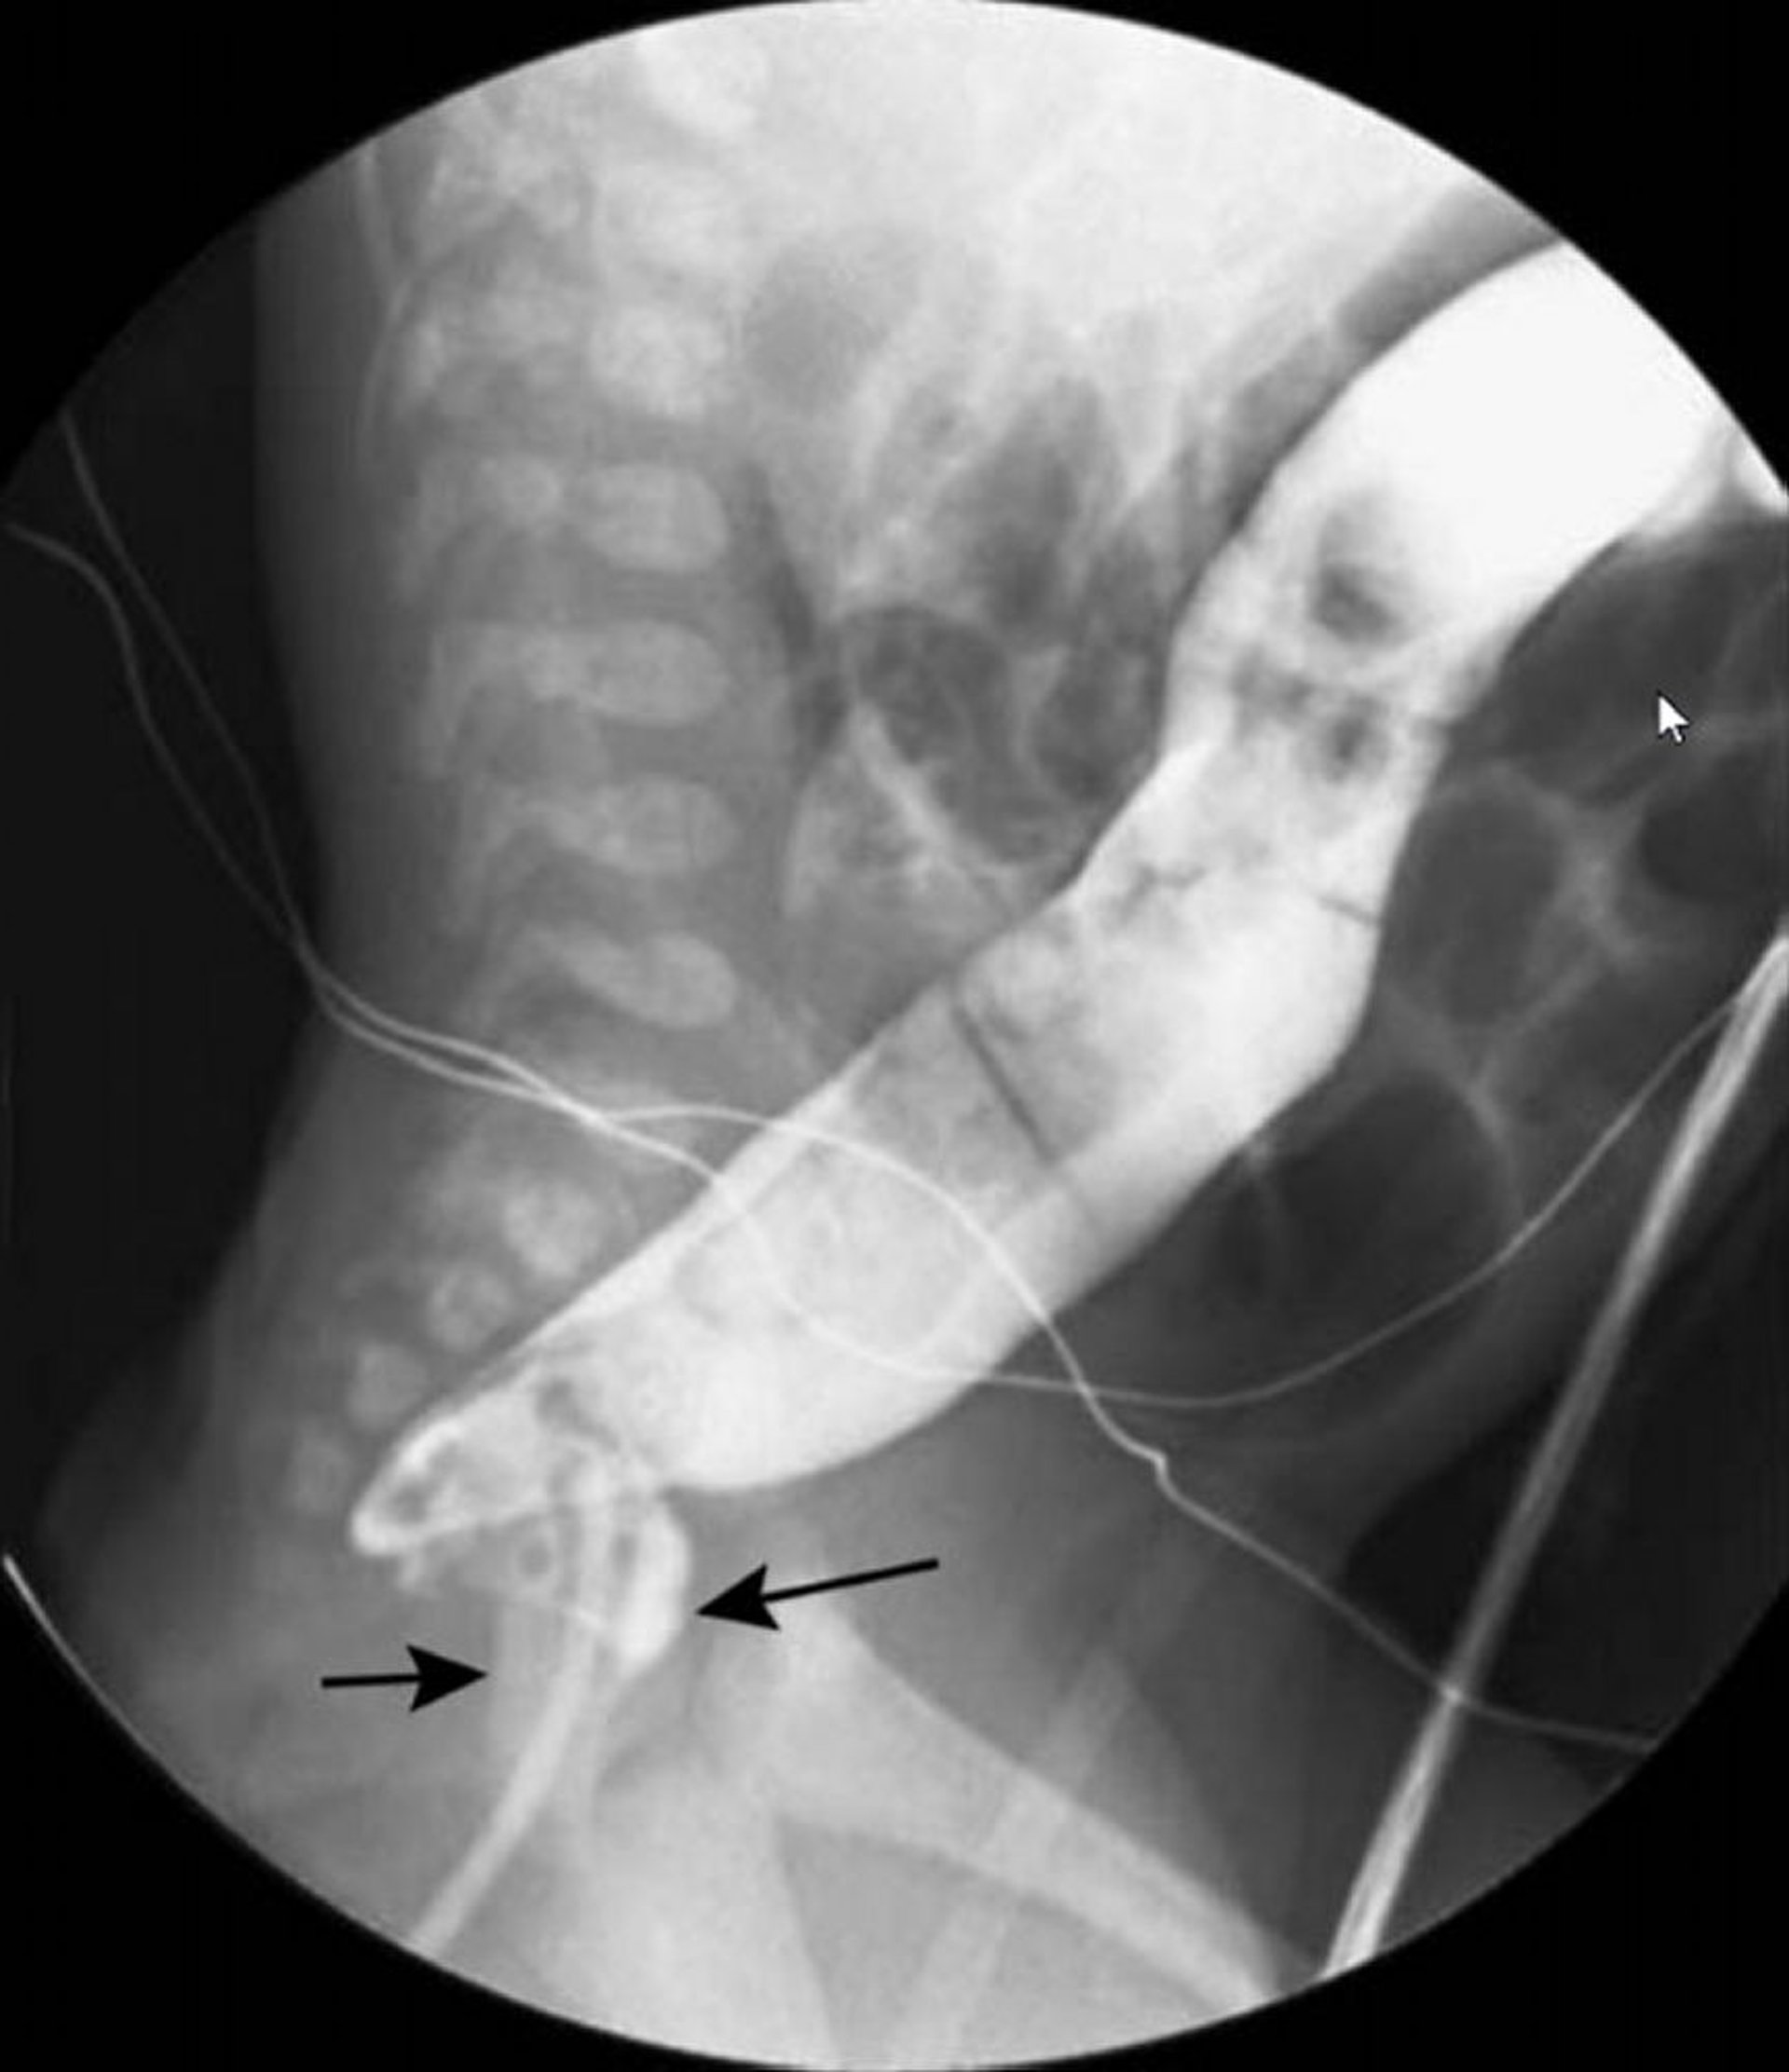

Single-Contrast Barium Enema Showing Swan Neck Appearance of Hirschsprung Disease

In this image, barium enema shows a narrowed rectum (black arrows) and a dilated colon (white arrow) more proximally.